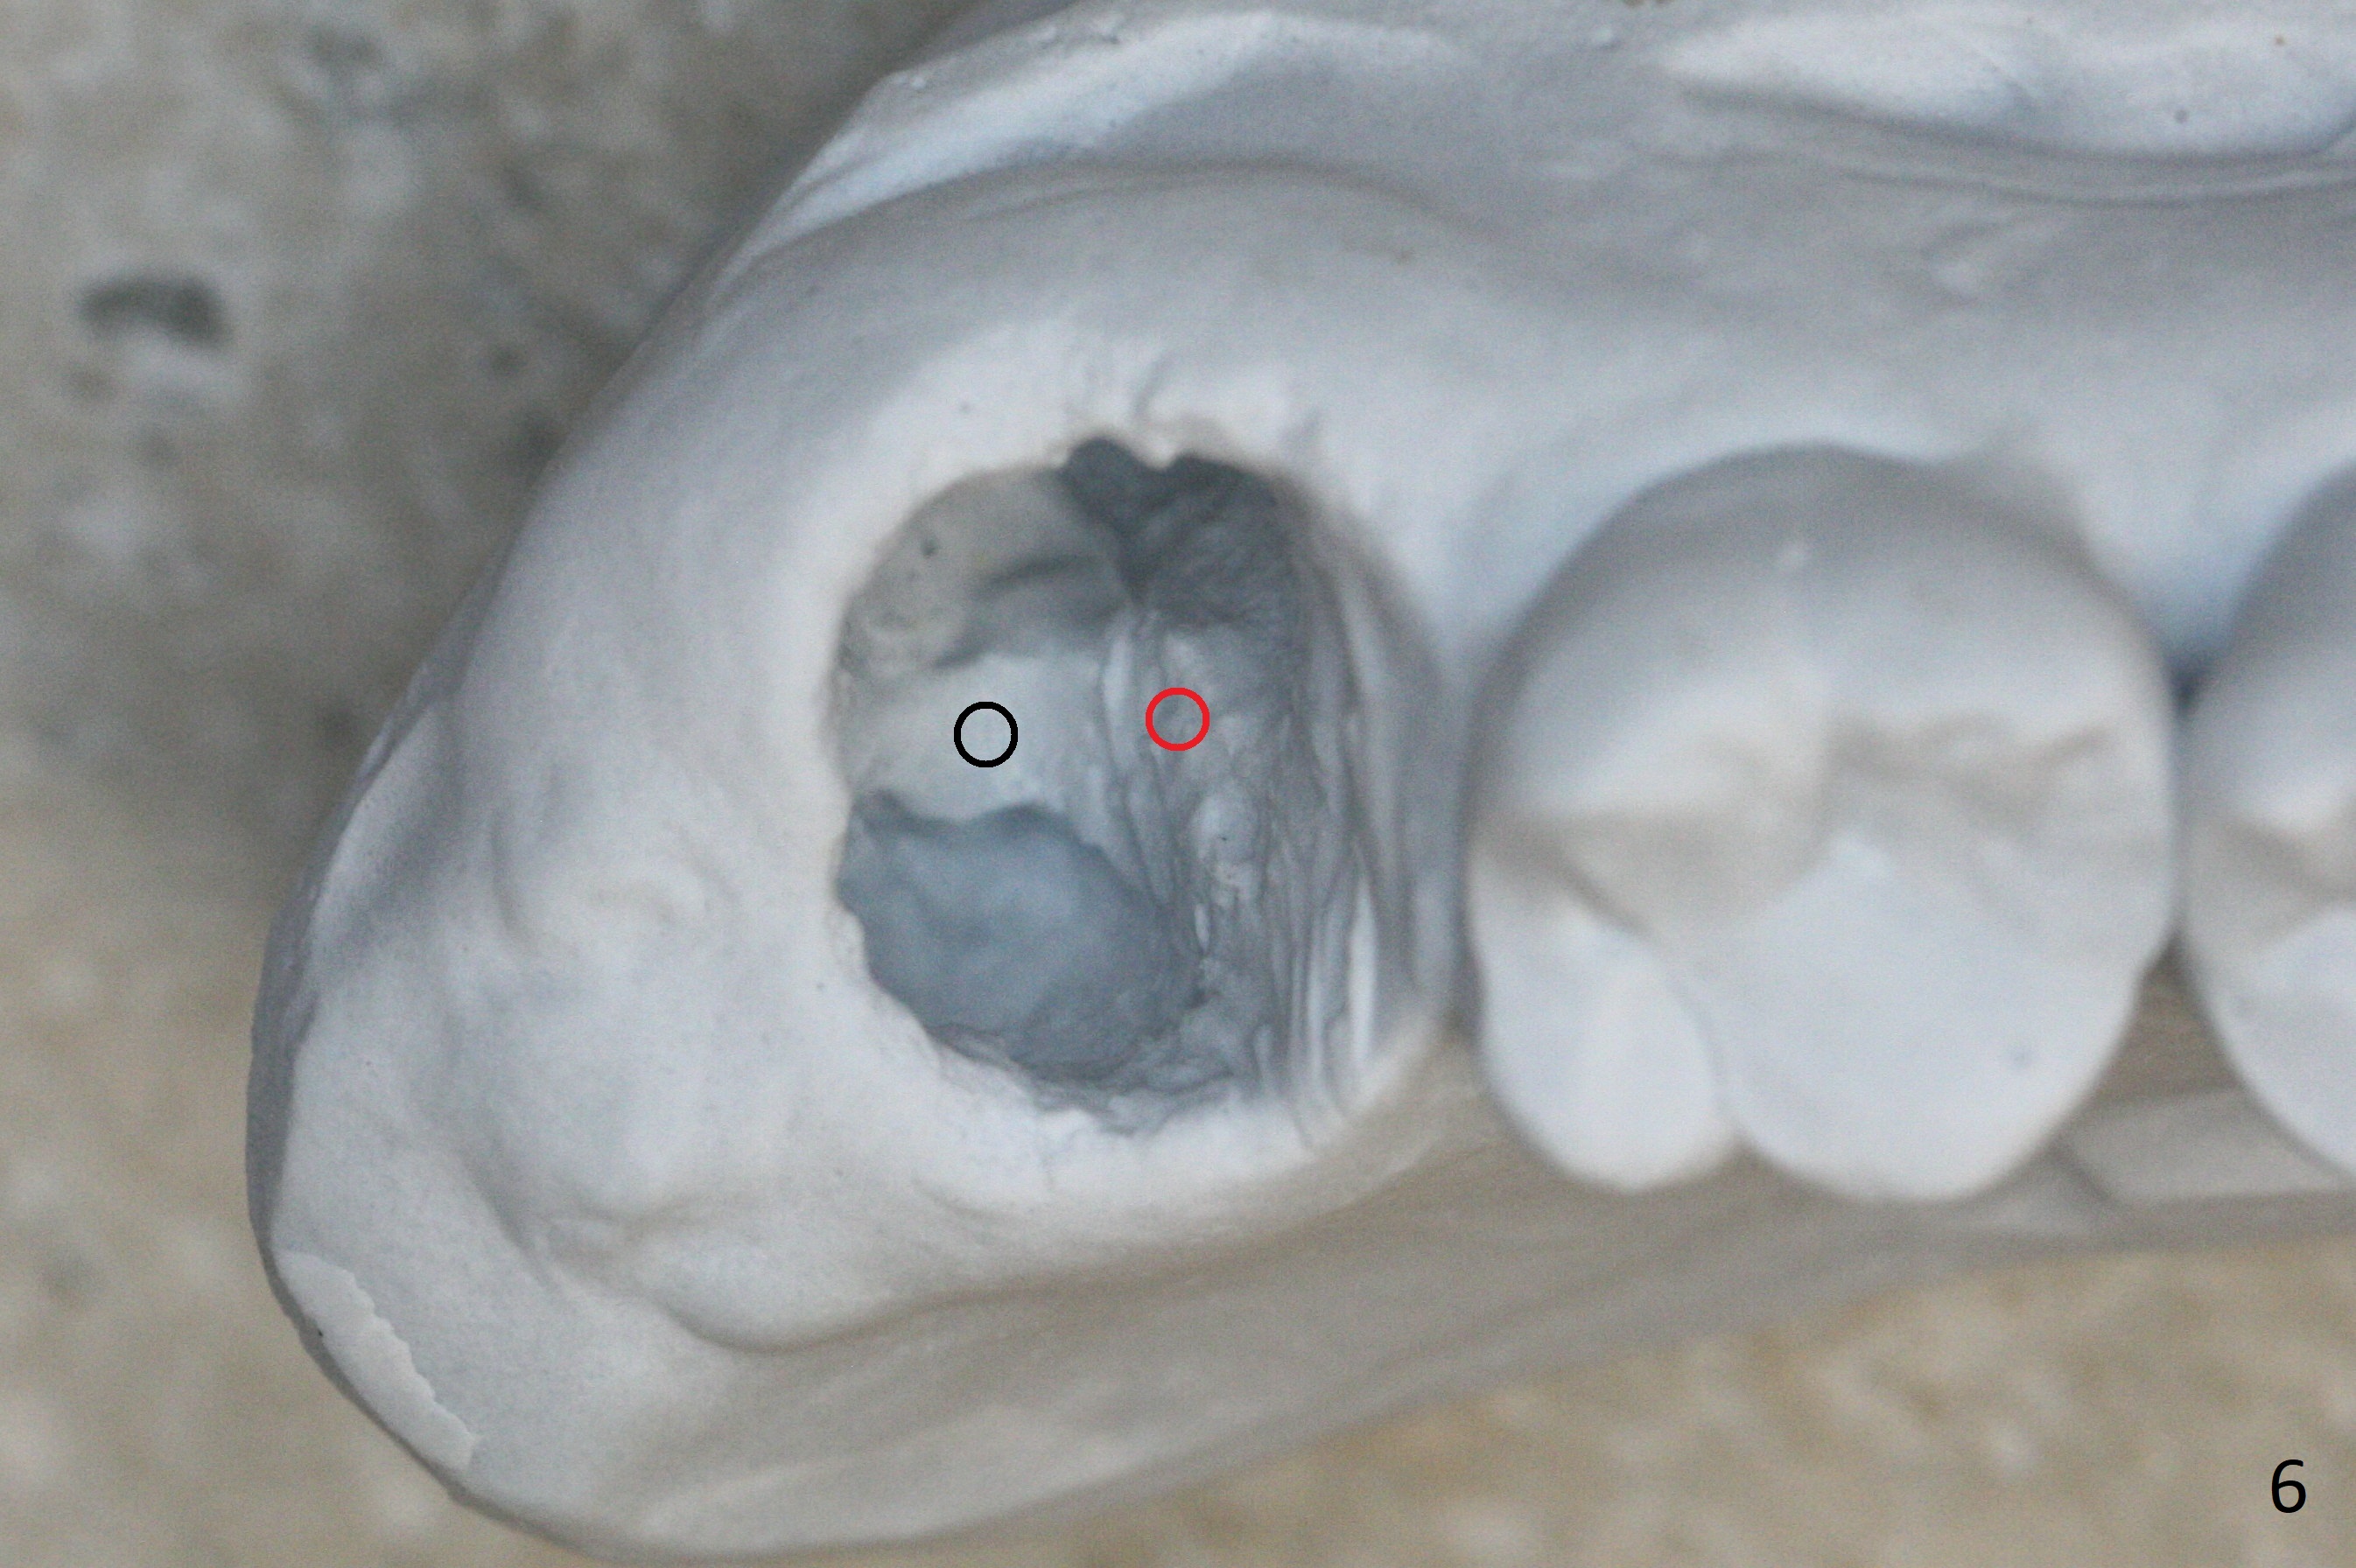

There is a fistula distal to the tooth #2 with deep pocket distopalatally (Fig.1 *), corresponding to palatal root fracture (Fig.2). There is a septum (Fig.3 S) between the buccal (B) and palatal (P) sockets. Osteotomy is initiated in the center of the septum (Fig.4 black circle). In fact the center of the socket is buccal (red circle), in which osteotomy should have been established because of the presence of the distopalatal bony defect associated with the root fracture and the distal fistula. The less ideal initial osteotomy leads to palatal placement of the implant and abutment (Fig.11 vs. 12).

Fig.5 shows the mesial slope of the socket (M), which is more or less the center of the socket mesiodistally. If the osteotomy were set up in the red circle (Fig.6) in the mesial slope (Fig.8 green dashed line), the trajectory of 4.5x11 mm dummy implant (Fig.7) would be more ideal (Fig.8 red outline) with more native bone contact. Finally a longer IBS implant is placed (4.5x15 mm, Fig.9,10) to achieve primary stability (50 Ncm). When the provisional is removed for impression 3 months 10 days postop, the implant is found to have been placed distopalatally (Fig.13), which should have been avoided. It appears essential to use guide for a distal implant. It is agonizing to re-encounter the off-axial implant (Fig.14) and the distopalatal access hole (Fig.15) 1 year post cementation. It is also amazing that the abutment screw has not loosened. A fair-sized piece of bone graft has just been removed buccally (Fig.15,16). The patient complains of sensitivity 2 years 3 months post cementation, although there is no abnormality around the implant crown. Guided surgery is essential to avoid restoration complication. There is no thread exposure nearly 3 years post cementation; in fact the apical portion of the abutment is covered by the bone (Fig.17,18).